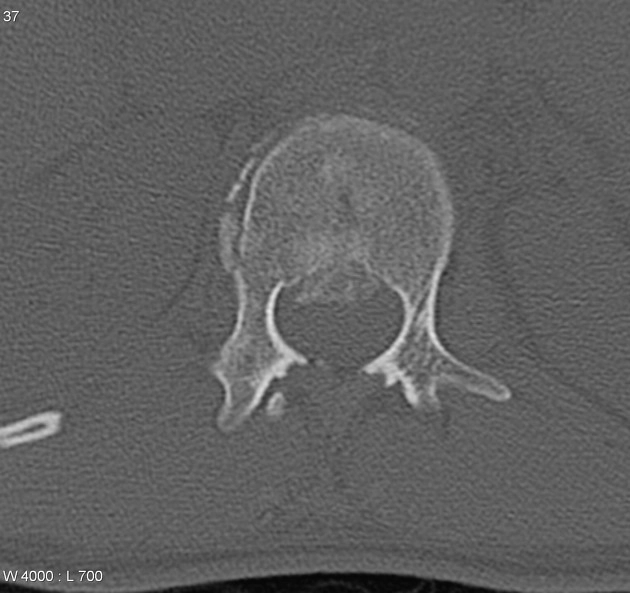

Gãy nát cột sống (Burst fracture)